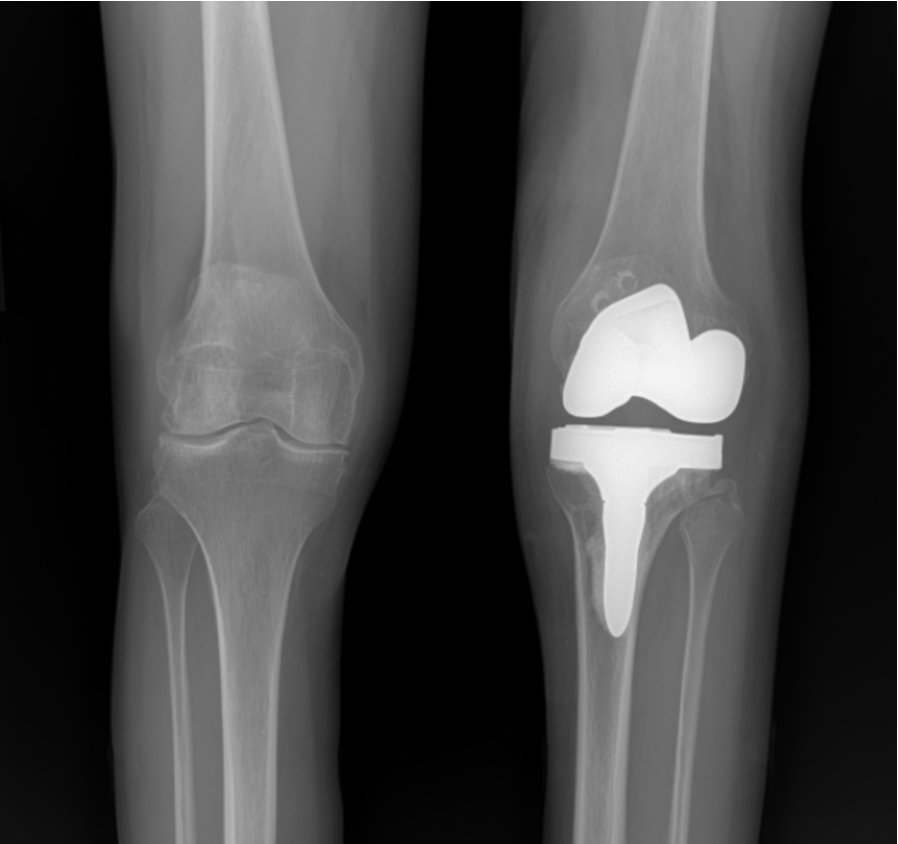

Read how a 67 year old lifelong baseball player returned to the field just one month after outpatient total knee replacement at MOR.

After years of JIA, Kelly became pain free through same day hip and knee replacements by Dr. Denis Nam at Midwest Orthopaedics at Rush in Chicago